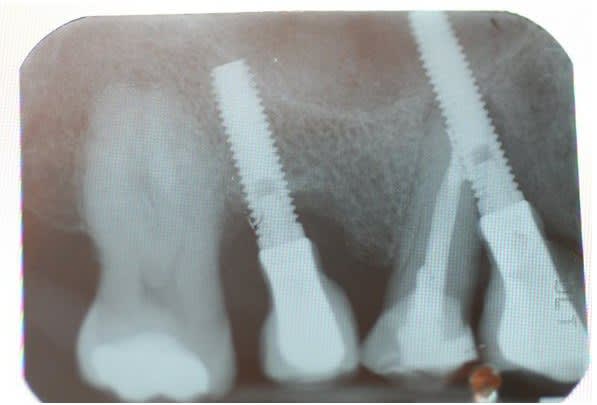

Mais un patient est arrive au cabinet avec 7 Implants maxillaires et rien de plus, bilan des courses , 2 mobiles, 2 avec l'hexagone externe cassé, 1 avec la vis prothétique cassée dans l'implant. Il reste un en place de 17 a moitie enterré et l'autre en 16, ni l'un i l'autre ont une vis de couverture ou un piler de cicatrisation.

La pano oui bof, les implants je pense des Klockner.

P.S : Pour le fun le cas pour lequel , je suis énervé et celui du proces est pire mais je ne peux pas le publier.

Il a laissé la patiente 5 mois comme ça en disant que tout allait bien, l'endo je l'ai faite moi au cas ou !!

Le second va être virer aussi car il est intra-sinusien générant une sinusite chronique.